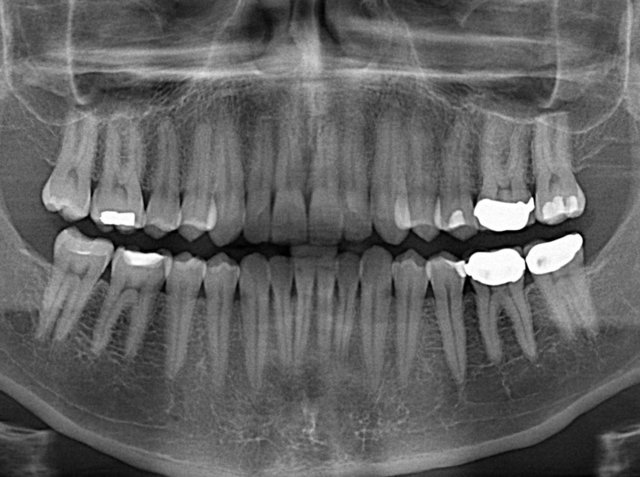

وی افزود: طبق آخرین پیمایشی که در خصوص وضعیت این بیماریها در کشور انجام شد، افراد میانسال به طور میانگین سه دندان پر شده، شش کشیده و چهار پوسیده دارند و میزان DMF در آنها حدود 13 درصد گزارش شده است. این شاخص در میان کودکان پنج تا شش ساله بالاتر از پنج است و نرخ آن از سال 77 تا 93 نسبتا صعودی بوده است. شاخص DMF در میان کودکان 12 ساله نیز در همین بازه زمانی از 1.5 به 2.9 درصد افزایش یافته است. آرزوی ما این است که پس از طرح تحول شاخص به کمتر از یک کاهش پیدا کند.

رییس شورای عالی سلامت دهان و دندان میانگین شاخص DMF در ایران را در سال شروع برنامه تحول سلامت دهان بالاتر از میانگین جهانی عنوان کرد و گفت: میانگین هزینه برای درمان پوسیدگی دندان کودکان پنج تا شش ساله که به طور متوسط 4.5 دندان برای هر کدام از آنها گزارش شده، هزار میلیارد تومان است. این رقم برای گروه سنی نوجوانان 12 ساله به 25 میلیارد و برای میانسالان 4800 میلیارد تومان برآورد میشود. همچنین جایگزینی دندانهای پوسیده در این گروه سنی 88 هزار میلیارد تومان هزینه لازم دارد، اما باید گفت که این موضوع در تمام دنیا به همین صورت است. در حال حاضر بیماریهای دهان رتبه دوم ابتلا به بیماریها را در دنیا به خود اختصاص دادهاند که منابع زیادی برای بهبود طلب میکنند.

رییس شورای عالی سلامت دهان و دندان ضمن اشاره به وجود 200 میلیون دندان پوسیده در دهان ایرانیان، اظهار کرد: عوامل خطر تاثیرات چندگانهای بر سلامت عمومی بدن دارند. یکی از مواردی که میتوان به آن اشاره کرد میزان استفاده از شکر در کشور است. در حال حاضر نیمی از جمعیت 15 تا 65 ساله کشور اضافه وزن دارند. همچنین پنج میلیون فرد مبتلا به دیابت در کشور زندگی میکنند و پنج میلیون نفر نیز در معرض خطر ابتلا به آن قرار دارند. مصرف روزانه شکر در کشور 66 گرم است؛ در حالیکه این رقم باید 40 گرم باشد. به همین منظور ما امسال پویش ملی کاهش مصرف شکر و روزانه دو بار مسواک را راهاندازی کردهایم.